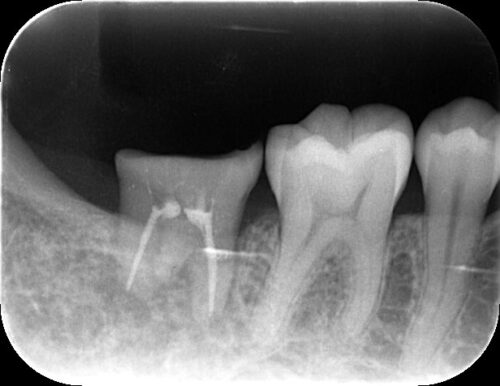

レントゲン写真を見ると、以前根管治療を受けて失活歯(神経が死んでいる歯)となっていたことがわかりました。

レントゲン検査を行い、破折の程度と周囲の骨の状態を確認しました。また、移植に使用できる親知らずについて評価しました。

赤い円で囲まれた部分に上顎の親知らずが存在していることが確認できます。

レントゲン写真で示されている上顎の親知らずを抜歯し、移植しました。

根管治療終了時のレントゲン写真です。移植歯の周りに骨ができ始めていることが確認できます。これは移植が成功し、歯が骨に定着し始めている証拠です。